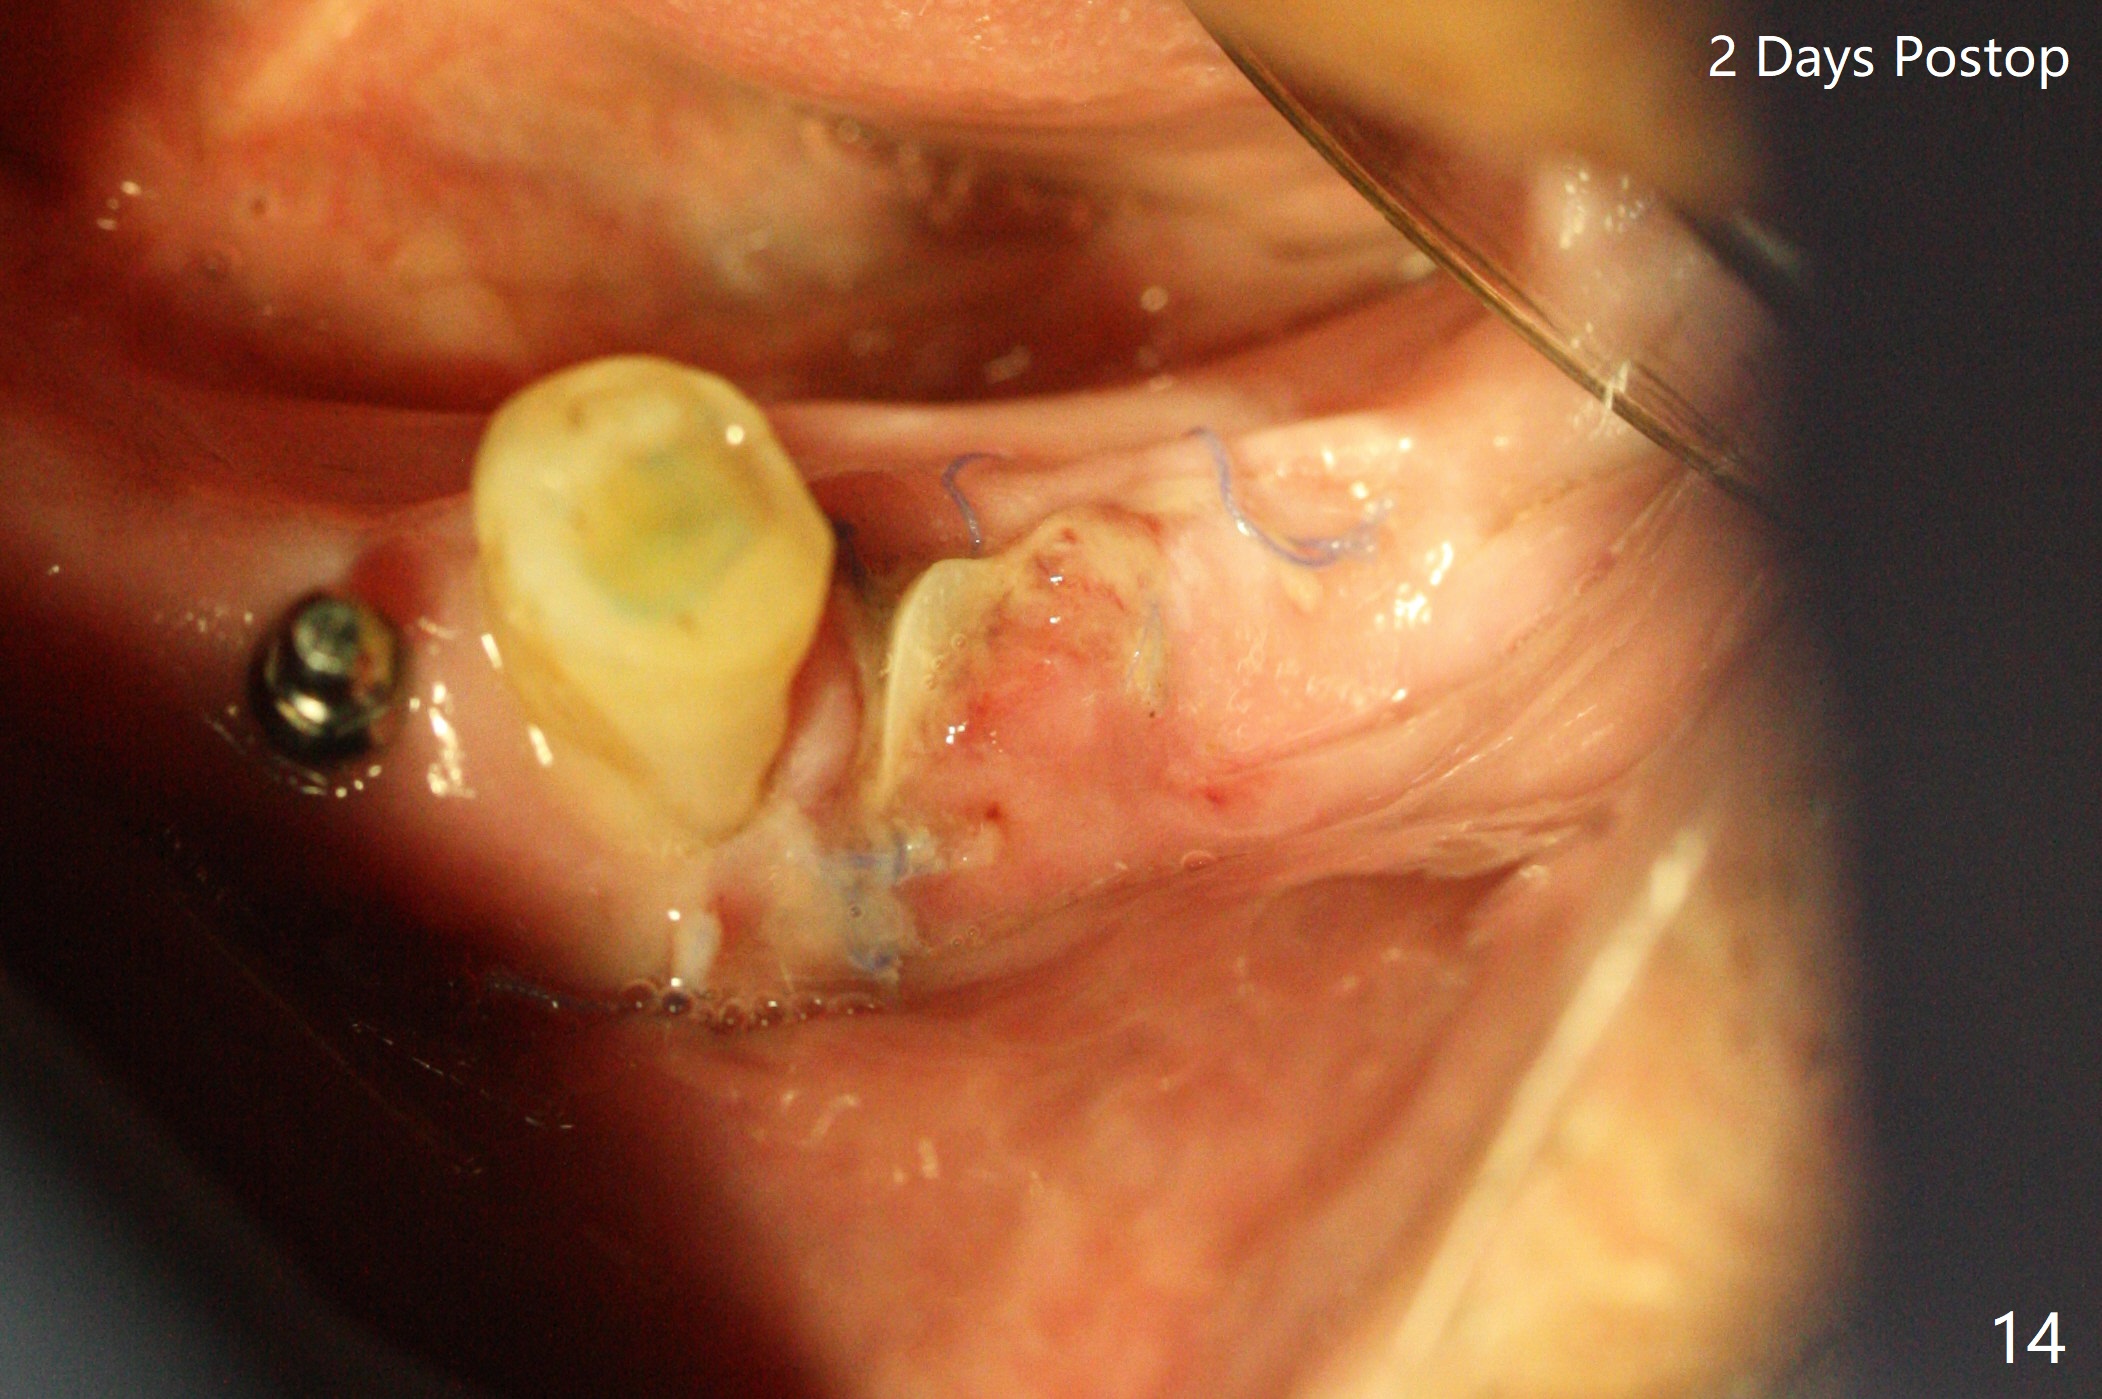

Three months post socket preservation (with buccal plate loss previously), a 3.5x11.5 mm implant is placed at #27 subcrestal (Fig.1). When implants are placed at #22 and 20 (Fig.2,4), threads are exposed buccal (B). Mixture of autogenous bone and allograft is placed to cover the exposed threads (Fig.3,5) following deep placement at #20. For safety, the implant at #20 is buried. Pain control at #18 is poor when initial osteotomy is being established (Fig.6 *), as related to severe infection. Repeated block anesthesia allows to finish implant placement with primary stability; a 3.5x2 mm ball abutment is placed (Fig.7). With placement of 2 other ball abutments at #27 and 22 (Fig.3), the lower existing RPD is converted to a removable provisional (Fig.8). With addition of acrylic, the socket of #20 is covered (Fig.9). There is no apparent bone #20 distal 3 months postop (Fig.10,11 <). Re-graft is needed? The implant at #21 appears immediately subgingival 5 months postop (Fig.12 *). The distobuccal threads are exposed (Fig.13). After decortication, allograft is placed, followed by 6-month membrane. In fact, a shorter and smaller implant should be placed instead. The patient has to wear the RPD for mastication. It would be more painful without it. Later the tissue surface of the RPD is trimmed.